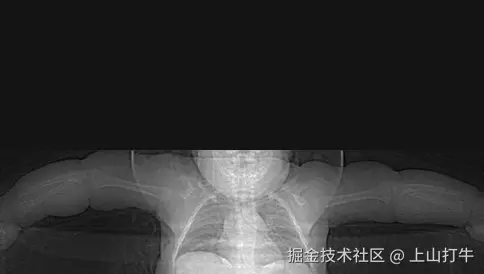

最终效果

image.png